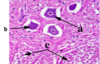

Identify the type of neurone arrowed at (a) and describe the appearance of its nucleus. What does this tell you about this cell’s activity?

Motor neuron cell body.The nucleus is large(white ring within the cell body). High quantity of rNA for high rate of protein synthesis.

The cell arrowed at b lacks a visible nucleus – what would this be called and why is a nucleus not present?

Motor neuron cell body sectioned in a plane away from its nucleus.

Imagine slicing through a boiled egg away from the yoke(nucleus).

What are the structures labelled c?

Neurological cells-cells that provide support and nutrition, regulate the internal environment of the brain

What are Nissl bodies and where would you find them?

Nissl bodies are the blue staining patches in the cytoplasm of the cell.These are aggregations of rough endoplasmic reticulum for high rate of protein synthesis.